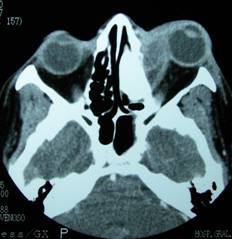

Infection is widespread affecting the orbital tissues. It is an acute infection, most frequently caused by sinus infections.

Orbital cellulitis affects the muscles, orbital fat, optic nerve and other orbital tissues.

It produces eyelid edema and redness with limitation of eye movements.

Often the existence of proptosis is evidenced, in which the eyeball tends protrude due to pressure from swollen orbital tissues.

The patient has fever, malaise.

It is a very serious disease with potential risk of eye loss, but also can lead to serious complications that endanger the patient's life such as cavernous sinus thrombosis, meningitis etc.

Prompt hospitalization and emergency treatment are required.

We must perform radiological tests such as CT scan, as well as microbiological sampling and be aware that this condition requires extreme vigilance.

We have to make differential diagnosis with other diseases such as orbital pseudotumour or abscess.